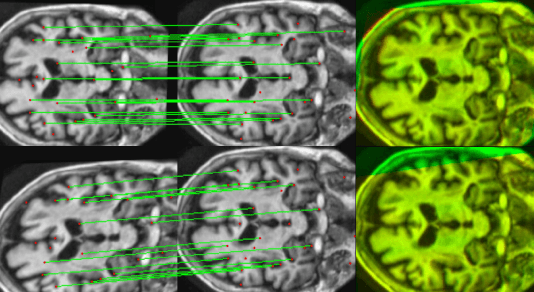

Abstract:We present WSSAMNet, a weakly supervised method for medical image registration. Ours is a two step method, with the first step being the computation of segmentation masks of the fixed and moving volumes. These masks are then used to attend to the input volume, which are then provided as inputs to a registration network in the second step. The registration network computes the deformation field to perform the alignment between the fixed and the moving volumes. We study the effectiveness of our technique on the BraTSReg challenge data against ANTs and VoxelMorph, where we demonstrate that our method performs competitively.